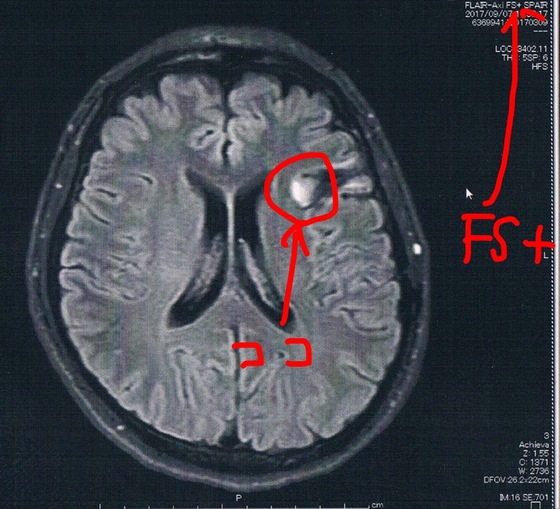

前回2017/9/7(手術後39か月)のMRI画像